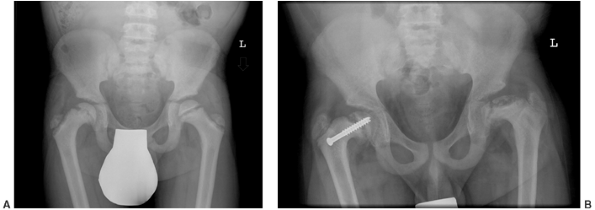

![]() |

Figure 7.8 Renal osteodystrophy in a 12-year-old boy. A:

An anteroposterior pelvis x-ray reveals an early slipped capital femoral epiphysis on the right. Slipped capital femoral epiphysis is common in renal osteodystrophy and rare in rickets. B: Three years after fixation the right proximal femoral epiphysis remains open and stable; the left hip now shows signs of epiphyseal avascular necrosis and fragmentation. |